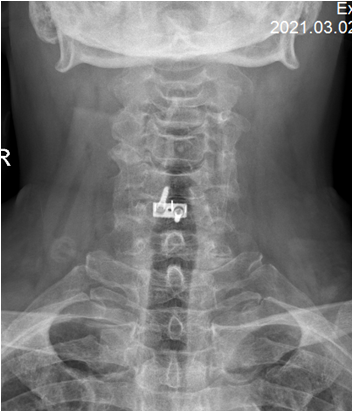

术后 图片1